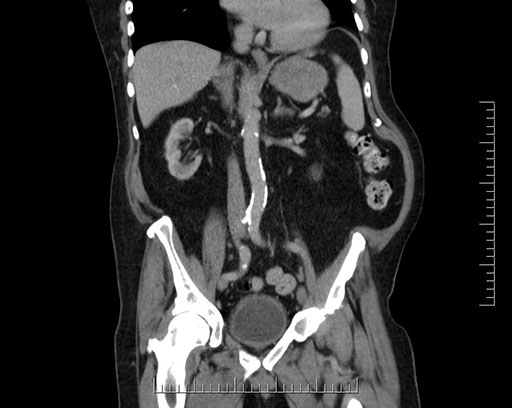

Whipple (pancreaticoduodenectomy) [case 7]

Imaging Analysis

Look through the patient's CT scan to identify any areas of concern for the necessary procedure.

Axial - 3 months prior